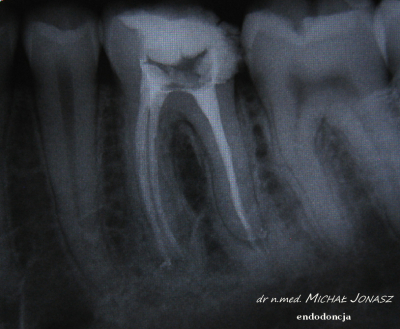

EXAMPLES OF ROOT CANAL TREATMENT PERFORMED BY OUR TEAM

Root canal treatment becomes necessary when the pulp of the tooth is attacked, that is, the tissue filling its interior, which is composed of blood vessels and lymphatic vessels as well as nerve fibers. In some cases, it happens that the tooth does not give pain, and yet there is an irreversible bacterial infection of the pulp. In most cases, patients requiring root canal treatment complain of acute pain in the affected teeth. Endodontic treatment is also necessary in some cases of tooth injury. This method of treatment is also sometimes used due to prosthetic indications. Infected dental pulp and pathological changes occurring in it are sometimes visible on the radiological image, which is performed before the procedure. Thorough cleansing, chemo-mechanical treatment of the root canal and its tight filling, for which special microscope is used, in the vast majority of cases leads to remission of bone changes and bone regeneration.

The root canal treatment method is selected depending on the severity of the inflammation. It is necessary to perform X-ray to determine the shape, length of the canal and the size of the infection. Then local anesthesia, opening the tooth cavity, removing the diseased pulp, cleaning, rinsing and drying the canal is performed. Root canal filling it with appropriate dental materials is the last step. Progress in dentistry allows to end up the treatment even on one visit.